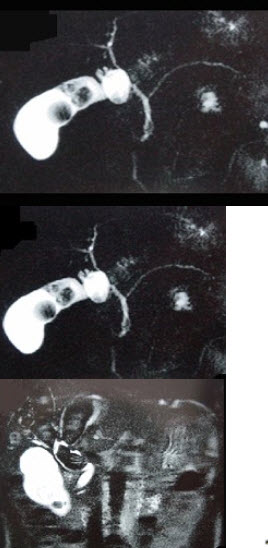

男,51岁,右上腹痛,Murphy征阳性,皮肤、巩膜无黄染,影像检查如图,最可能的诊断是( )

A:胆囊癌

B:胆囊息肉

C:胆囊结石

D:胆囊腺肌增生症

E:慢性胆囊炎